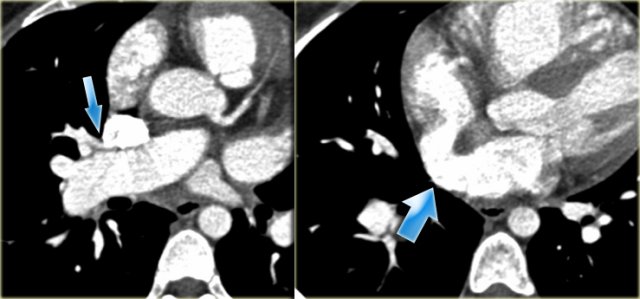

Patent Ductus Arteriosus Patent Ductus Arteriosus

Patent Ductus Arteriosus

On the left an adolescent with a murmur.

On axial image and reconstruction the patent ductus arteriosus is seen.

The ductus arteriosus is the communication between the pulmonary artery and the proximal descending aorta.

It shunts blood in utero from the right ventricle to the aorta to bypass the non-functioning lungs.

On the first day of life there is a functional closure and an anatomic closure with fibrosis in the first two weeks.

If it does not close these patients come to attention either with a murmur or later with pulmonary hypertension.

On the left a young adult with a murmur.

The cardiologists are not interested in the flow direction, but just want to confirm the diagnosis.

Notice the connection between the pulmonary artery and the descending aorta.

When the duct closes it may also calcify.

This a normal variant.